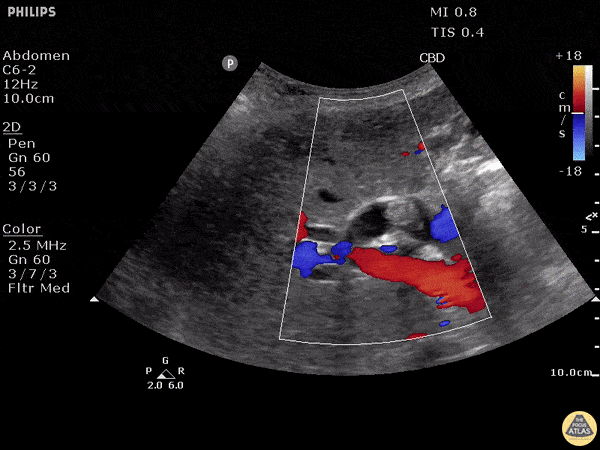

Biliary - Choledocholithiasis - Dilated Common Bile Duct with Stone

A normal common bile duct should be < 4mm plus 1mm per decade after 40 years of age. A stone can clearly be seen in the area of color flow doppler. The bile duct is obviously dilated here (although not measured). When searching for the CBD, it can be useful to turn color flow doppler on to ensure you're visualizing a biliary structure and not vessels. This technique was employed here. POCUS is highly sensitive for acute cholecystitis but as many people already know, it can be hard to find the CBD, which is reflected in the lower sensitivity and specificity for this indication in many studies. Justin Bowra MBBS, FACEM, CCPU Emergency Physician, RNSH et al. (Dr. Dop Ahilan)